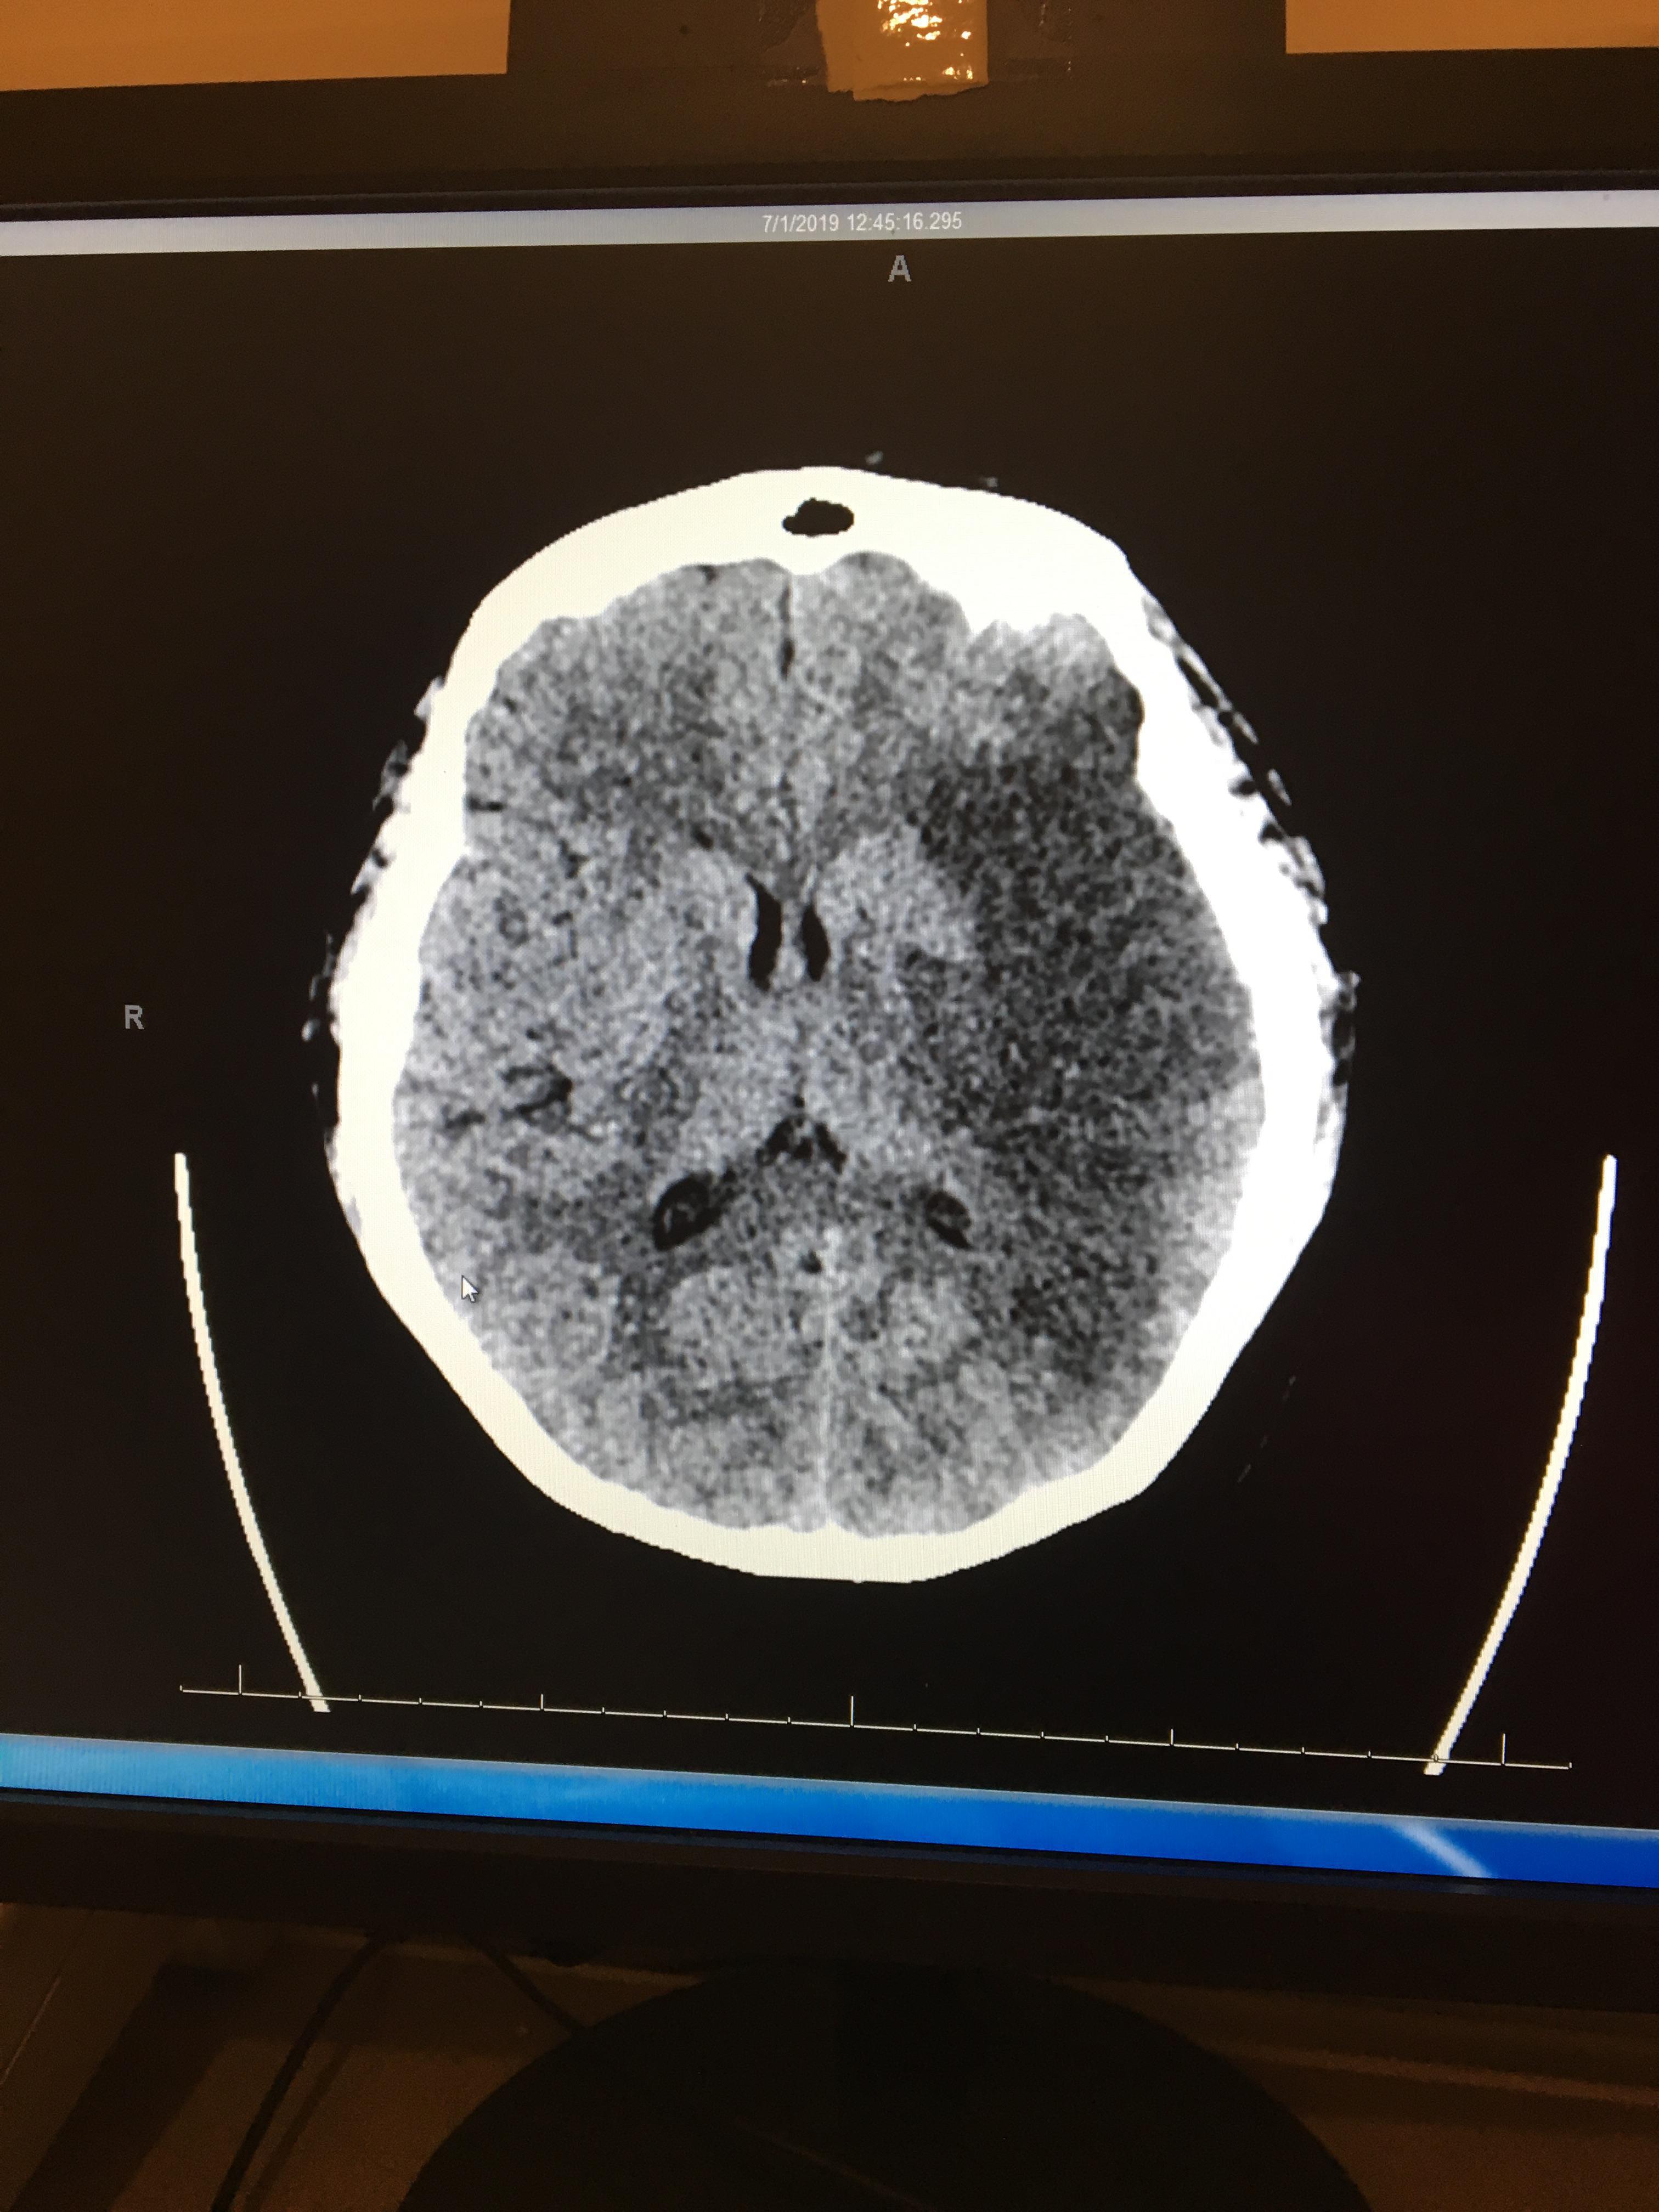

And on June 30th Rochelle had a massive stroke, she was found on the floor of her home by her sons who immediately called 911.